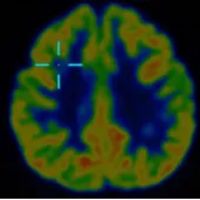

借助医院先进的高清晰度、高对比度薄层扫描核磁共振,配合PET-CT检查,终于在右额叶发现了一个极其微小的致痫病灶。这个位置,与脑电图提示、以及临床发作特征完美吻合。更幸运的是,虽然病灶位置深,但范围很小。

640_副本

640 (1)_副本

这一发现,为精准治疗打开了大门。